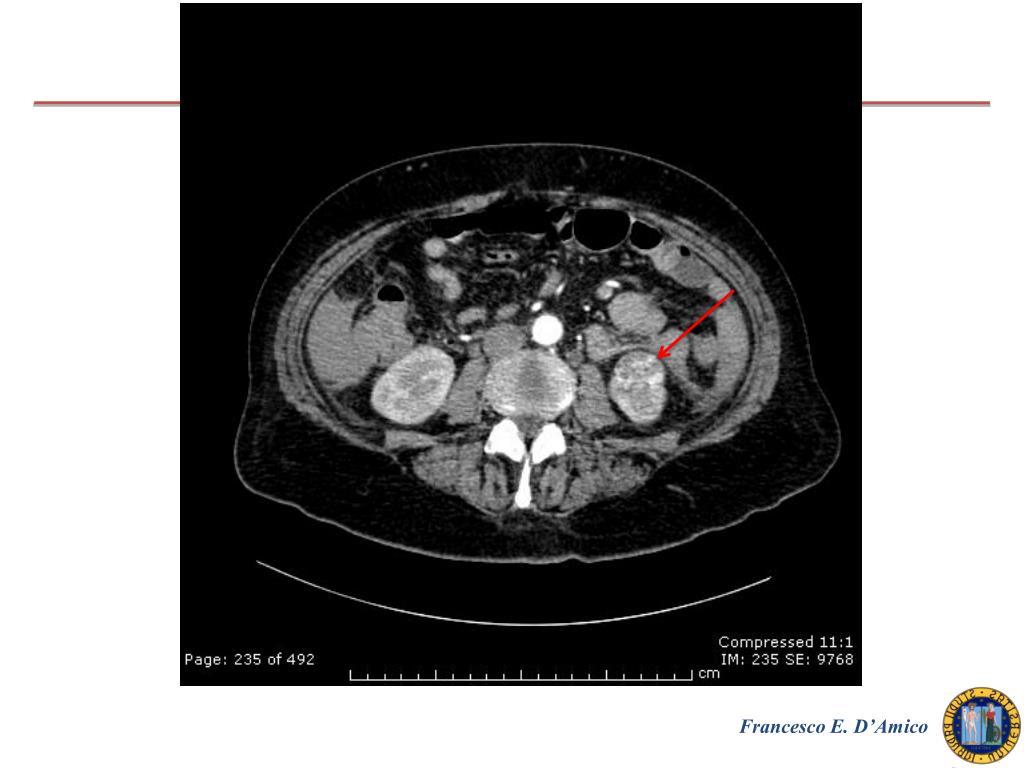

2. G. M. 62 anni donna Anamnesi Epicrisi Colecistectomia VLS Sdr di Sjogren diagnosticata nel 2010 (in terapia corticosteroidea) 23.10 : ricovero per sospetta sepsi da infezione delle vie urinarie (Febbre con brivido, leucocituria) Esami ematochimici all’ingresso Hb: 13,1 g/dL, GB 13000, PCR 190 mg/, ALT 21 U/L Dolori addominali ed anemizzazione Ecoaddome: falda di versamento in tutti i recessi TC addome Francesco E. D’Amico

3. Francesco E. D’Amico

4. Francesco E. D’Amico

5. Francesco E. D’Amico